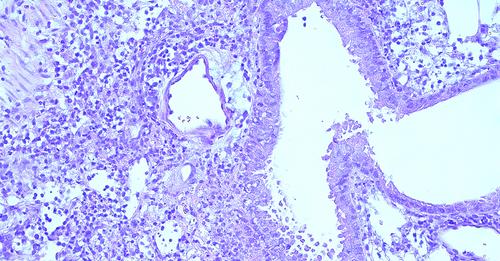

➡️ Une étude réalisée par des chercheurs du département des maladies infectieuses (FARAH/Faculté de médecine vétérinaire Université de Liège) vient de mettre en évidence le rôle important des monocytes Ly6Chi dans la régulation des réponses immunitaires au niveau de certaines maladies infectieuses.

➡️ "Au cours de l’étude que nous venons de publier dans Science Immunology, explique Bénédicte Machiels, Chercheuse qualifiée F.R.S.-FNRS FNRS à l' Université de LiègeUniversité de LiègeUniversité de Liège, nous nous sommes intéressés aux mécanismes régulateurs induits par des virus persistants, les gammaherpèsvirus (γHVs) - des virus extrêmement prévalents tant chez l’homme que chez l’animal- ayant co-évolués avec leur hôte depuis des millions d’années."